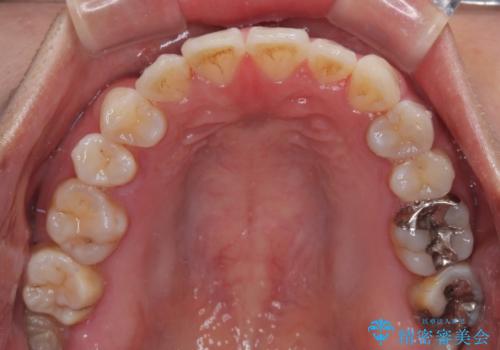

上下前歯のデコボコを気にして来院された患者様です。

ワイヤー矯正でもマウスピース矯正でも可能でしたが、短期間で、自身の手を煩わせることなく治療を行いたいとのことで、ワイヤー装置にて矯正治療を行うこととしました。

舌の突出癖により、治療過程でスペースが多くできましたが、舌のトレーニングを頑張っていただき、1年強で終えることができました。